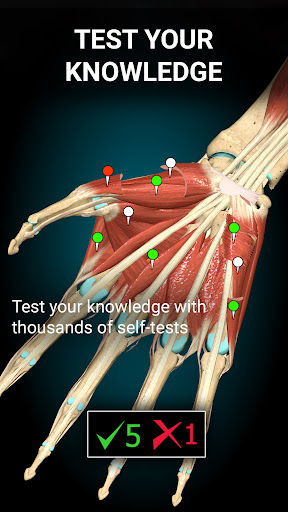

★ 3D location quizzes to test your knowledge

- Added QUIZ tab, with more than 1000 quizzes

- Added QUIZ tab, with more than 1000 quizzes

- Added QUIZ tab, with more than 1000 quizzes

- Added QUIZ tab, with more than 1000 quizzes